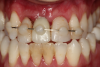

Fig 6. Image of the patient’s mature smile.

Figure 6